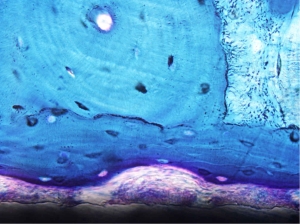

Valutazione dell’osteointegrazione dei biomateriali utilizzati in chirurgia protesica con o senza adiuvanti biologici - L’osteointegrazione degli impianti è un requisito fondamentale per il successo della chirurgia ortopedica ricostruttiva e le caratteristiche di superficie dei biomateriali influenzano notevolmente i processi di osteointegrazione e, di conseguenza, il successo o il fallimento della chirurgia ortopedica nei pazienti. I progetti hanno lo scopo di migliorare le conoscenze sulla fisiopatologia degli impianti ossei e di studiare i diversi biomateriali per la realizzazione di impianti protesici in grado di accelerare i processi di crescita ossea e migliorare la qualità e la maturazione dell’osso neoformato attorno agli impianti. Particolare interesse è posto alla possibilità di stimolare le proprietà intrinseche di rigenerazione ossea attorno ad un impianto attraverso l’utilizzo di fattori biologici quali fattori di crescita, plasma ricco di piastrine, derivati ossei e cellule staminali mesenchimali.

Studio di biomateriali a differenti caratteristiche chimico-fisiche e morfologiche per la realizzazione di dispositivi protesici in osso sano e patologico - E’ noto che la risposta di cellule e tessuti a biomateriali è notevolmente influenzata dalle proprietà di superficie. Per tali motivi, l’interesse è rivolto allo sviluppo ed alla valutazione biologica di nuovi trattamenti in grado di modificare la superficie di protesi ed impianti quali i metodi biochimici che permettono di immobilizzare proteine, enzimi o peptidi sulla superficie dei materiali e le proprietà topografiche (porosità, micro o macro rugosità, nanostruttura) con lo scopo di indurre una specifica risposta cellulare e tessutale. Infine, particolare importanza viene rivolta alle proprietà del tessuto sede dell’impianto con allestimento di modelli patologici specifici (es. osteoporosi da carenza estrogenica, da invecchiamento o secondaria ad altre patologie) ove vengono testati i biomateriali innovativi in condizioni sperimentali che simulano la situazione clinica di pazienti che sempre con maggiore frequenza risultano affetti da patologie che influenzano il metabolismo osseo.

Studio di biomateriali a differenti caratteristiche chimico-fisiche e morfologiche per la realizzazione di dispositivi protesici in osso sano e patologico - E’ noto che la risposta di cellule e tessuti a biomateriali è notevolmente influenzata dalle proprietà di superficie. Per tali motivi, l’interesse è rivolto allo sviluppo ed alla valutazione biologica di nuovi trattamenti in grado di modificare la superficie di protesi ed impianti quali i metodi biochimici che permettono di immobilizzare proteine, enzimi o peptidi sulla superficie dei materiali e le proprietà topografiche (porosità, micro o macro rugosità, nanostruttura) con lo scopo di indurre una specifica risposta cellulare e tessutale. Infine, particolare importanza viene rivolta alle proprietà del tessuto sede dell’impianto con allestimento di modelli patologici specifici (es. osteoporosi da carenza estrogenica, da invecchiamento o secondaria ad altre patologie) ove vengono testati i biomateriali innovativi in condizioni sperimentali che simulano la situazione clinica di pazienti che sempre con maggiore frequenza risultano affetti da patologie che influenzano il metabolismo osseo.